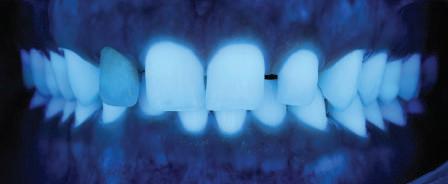

Една седмица след препарацията на зъбите и циментирането на цирко ниевото кепе бяха изработени 12 IPS Empress Cad Multi фасети. Макро- и микротекстурата на фасе тите бяха направени на ръка, след кое то бяха нанесени 3D характеризации с боички, а полирането отново бе напра вено ръчно, за да им се придаде естест вен и естетичен вид. Предизвикателството тук беше короната да има същите оптични характеристики като тези на остана лите зъби при естествена светлина, през поляризационен и флуоресцентен филтър. 3D принтерът бе Fromlabs, софтуерът за фрезоване – Mill Box, а фрез апаратът –imes icore CORiTEC 350i. В крайна сметка постигнахме ес тествен вид на усмивката с натурал на зъбна морфология при изцяло диги тален протокол, при който дизайнът бе направен първоначално и през всич ки етапи на лечението се придържахме към него до самия край Излишно е да отбелязваме, че всички сме удовлетворени от постигнатото! Преди След Победител в категория „Клиничен случай с изцяло дигитален протокол“ в конкурса „Усмивка на годината 2022“

11Dental Tribune Bulgarian Edition / октомври 2022 г. Преди лечението Фиг. 1 Фиг. 2 Фиг. 3 Фиг. 4 Фиг. 5 Фиг. 6 Фиг. 7 Фиг. 9 Фиг. 10 Фиг. 11 Фиг. 8 Фиг. 12 Фиг. 13